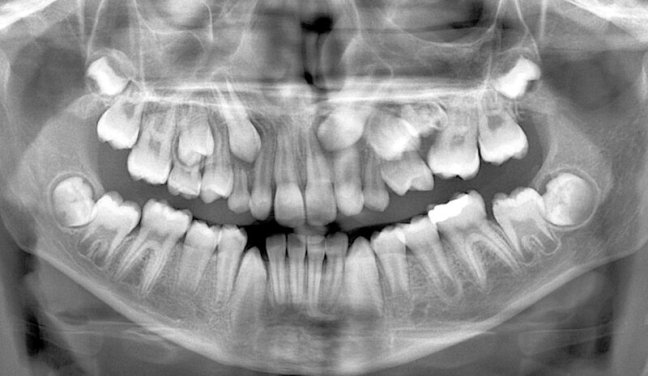

Umur yang ada di tabel di atas bisa jadi patokan tentang waktu pertumbuhan gigi. Tapi bukan harga mati, karena umur dentalis setiap anak beda-beda, jadi jangan langsung panik kalau tumbuh giginya gak sesuai ‘jadwal’. Kalau telatnya telat banget, masuk hitungan tahun atau sampe mau masuk SMP masih ada gigi yang belum tumbuh, datanglah ke dokter gigi, selanjutnya bisa dilakukan foto panoramik untuk melihat ada atau tidaknya benih gigi.